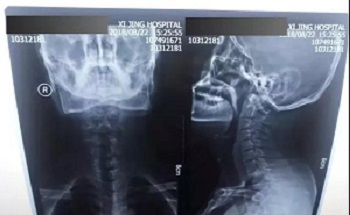

八、拍片子时,如果一张片子上有两张图像的时候,合起来拍一张,分开再各拍一张(如以下三张)